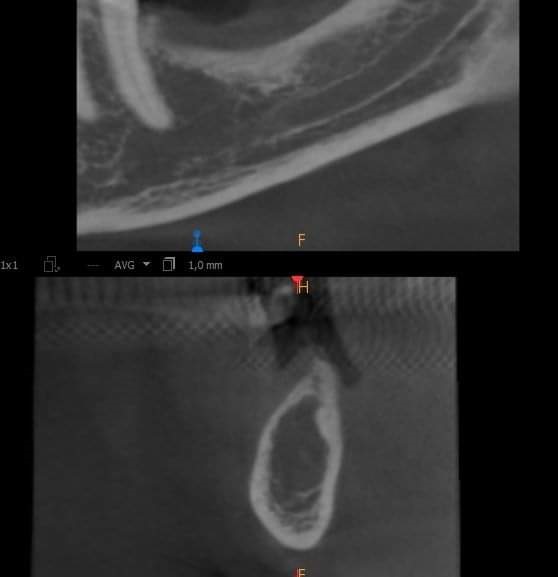

Questa l’immagine che mi ha mandato in zona 36.

Come puoi vedere del nervo non c’è traccia.